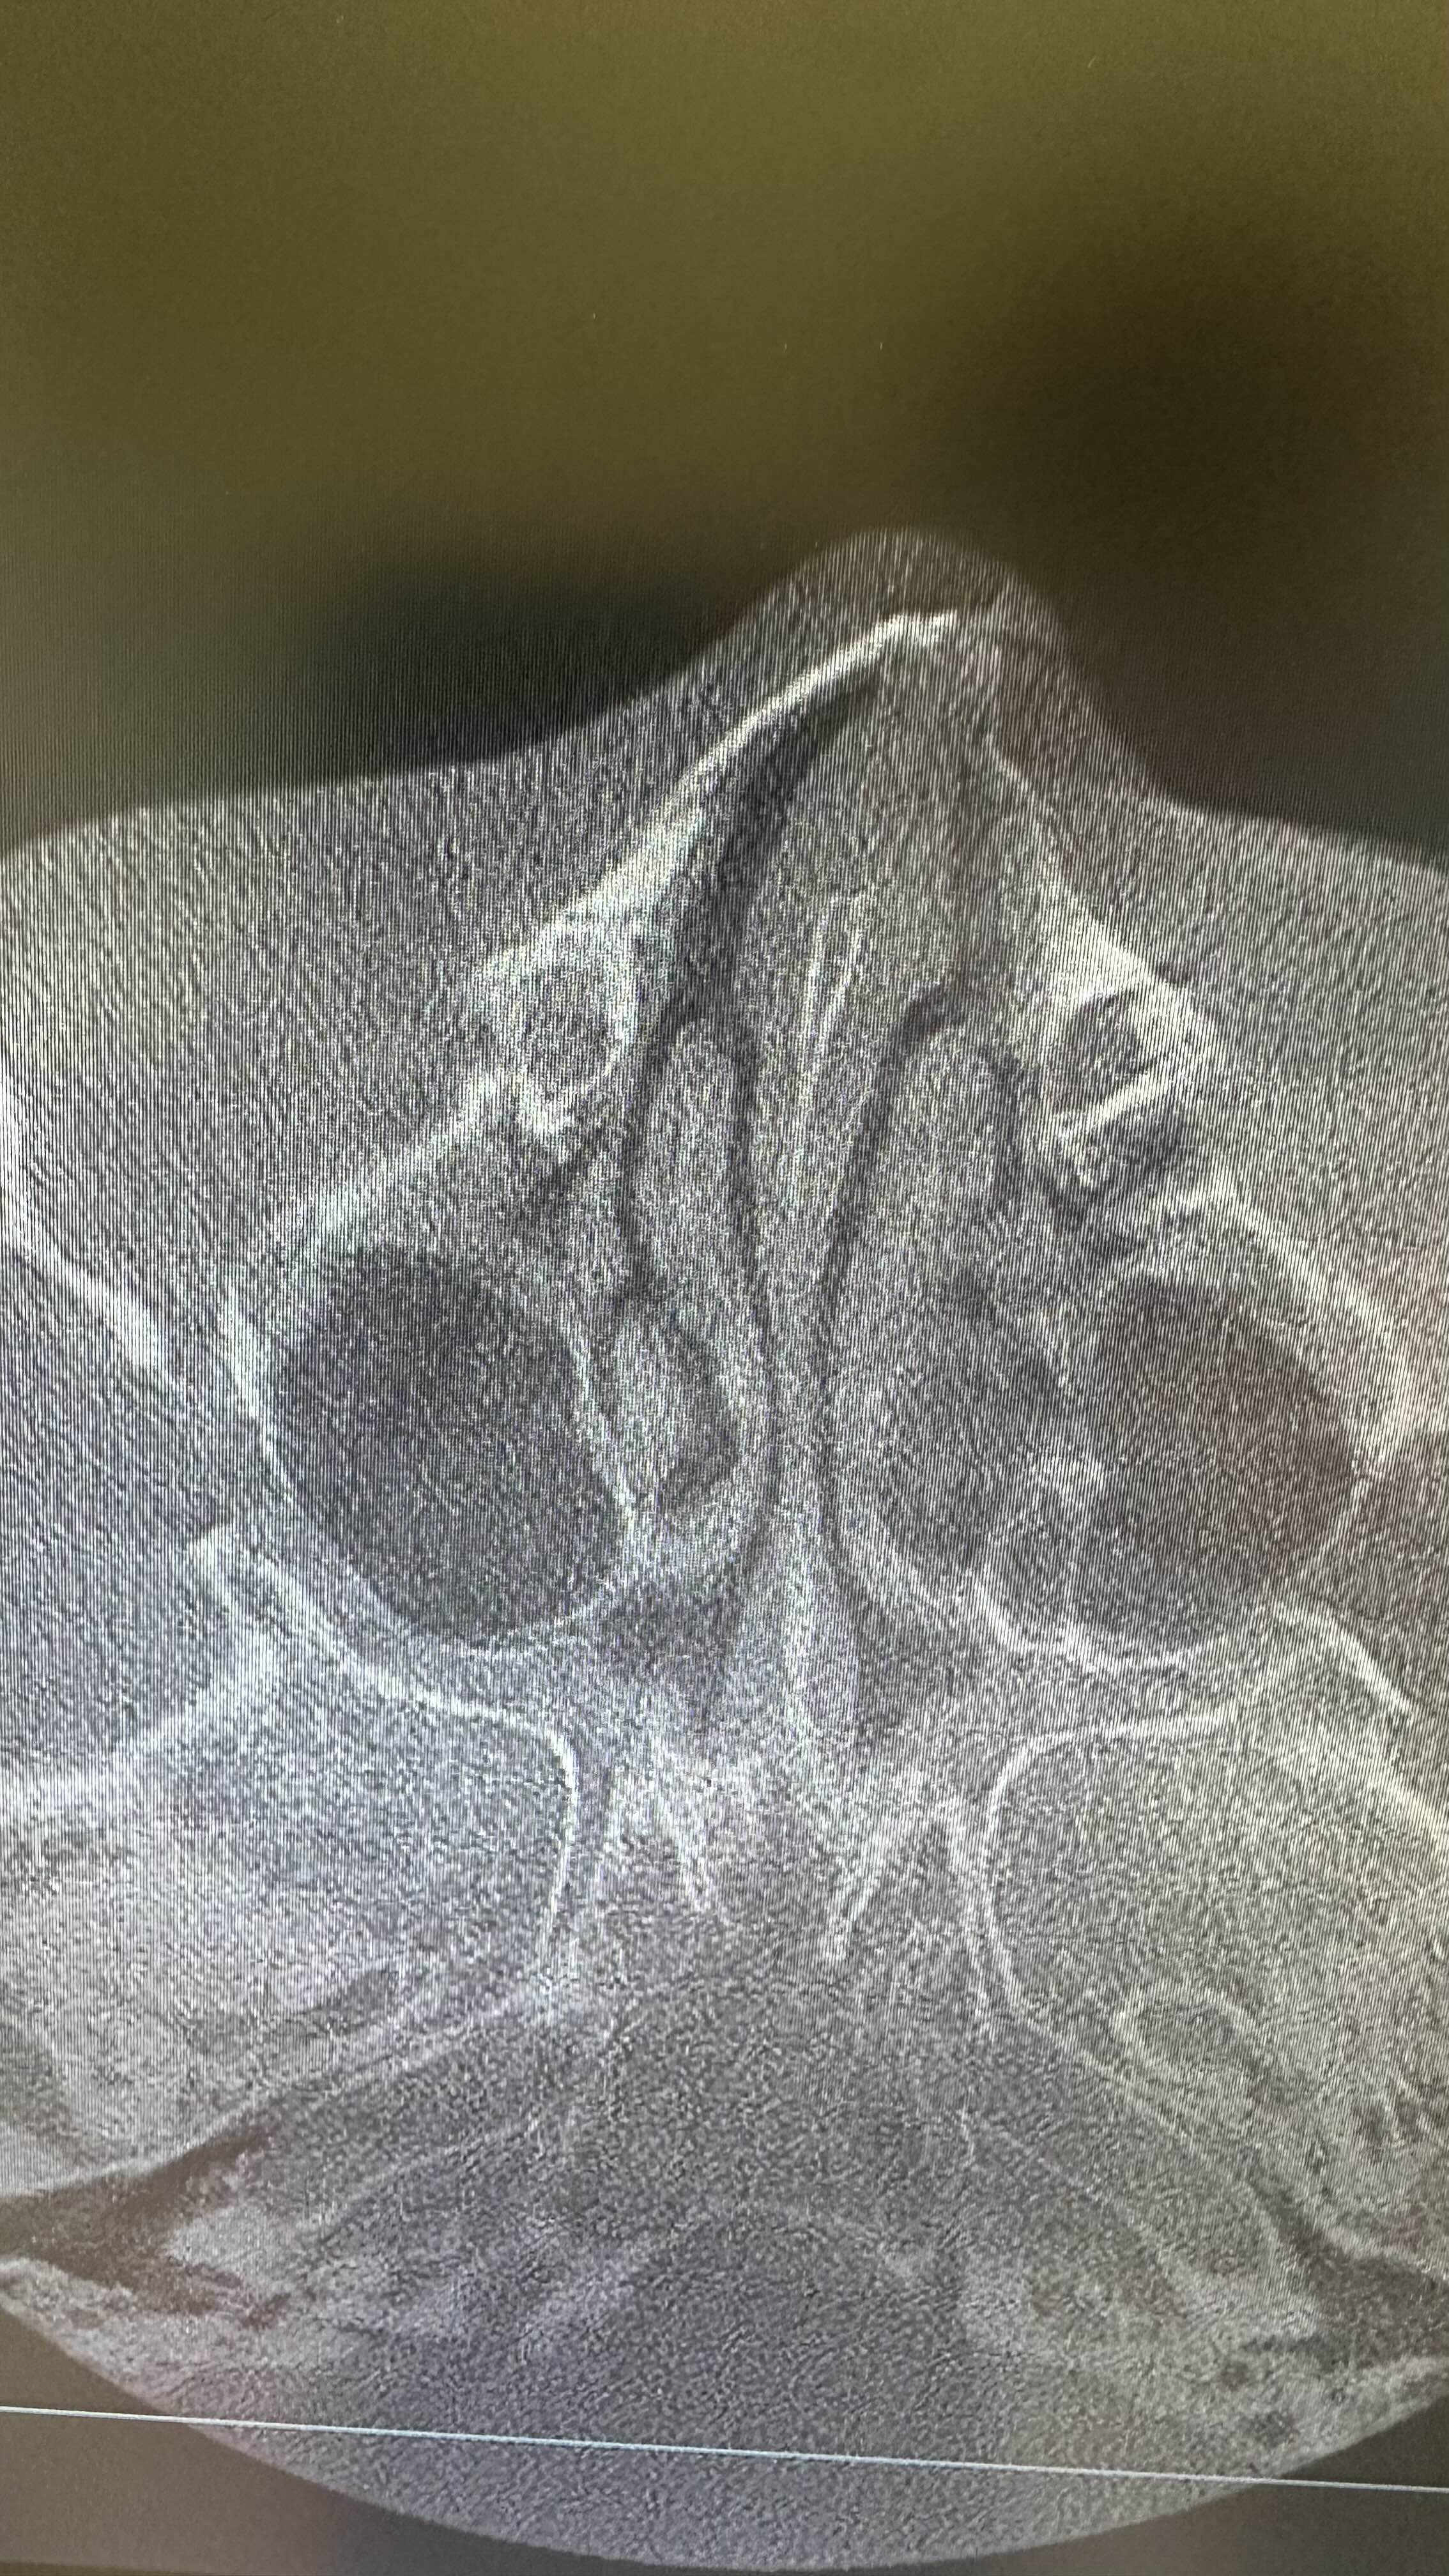

병원에 가서 엑스레이 찍어보니

한국에 와서 CT를 찍어보니

3조각 이상으로 부서졌다네요.

의사샘 말로는 박살났다고 ㅠㅠ